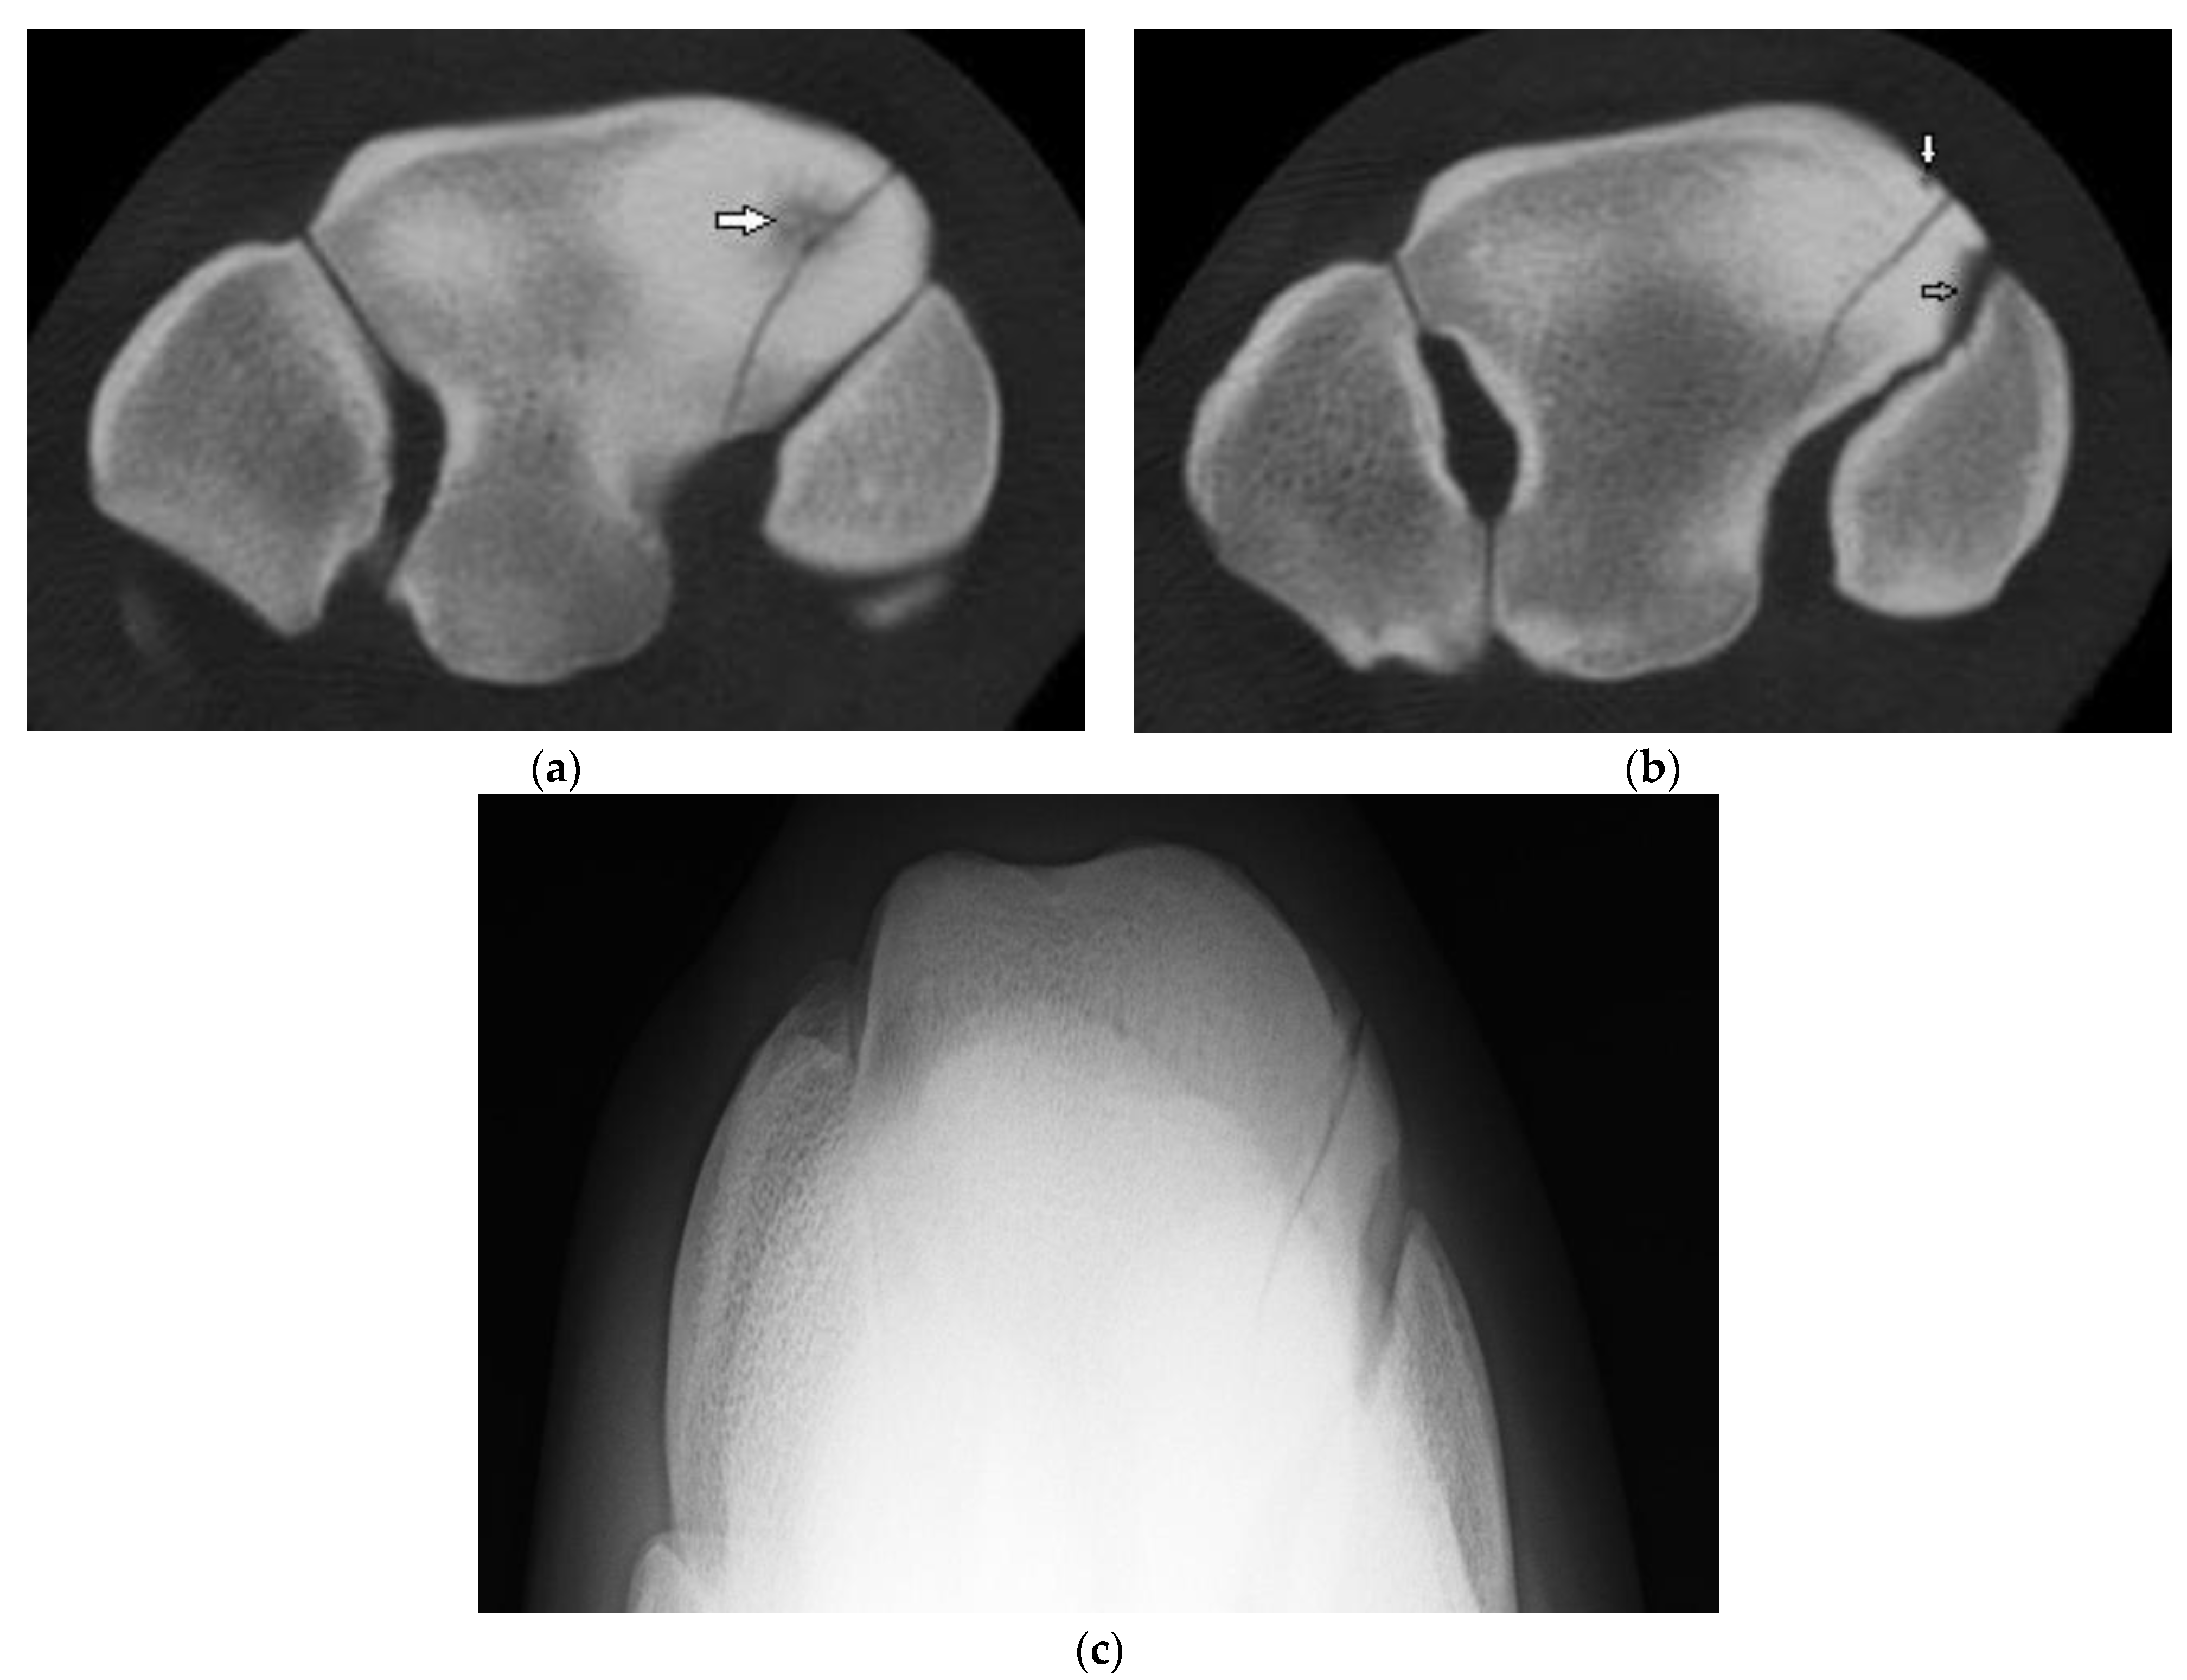

Horses ranged in age from 2 to 7 yr (mean 4.27 yr) for cases and 1 to 6 yr (mean 3.2 yr) for controls. Film radiographs (XR) were available for the fractured carpus of all 15 horses, and of the contralateral carpus in 6 horses. CT was available of the contralateral carpus of 13 horses. Fracture cases included 2 incomplete and 13 complete Fx, either frontal (n = 13) or corner (n = 2), and ranged from simple to severely comminuted. Signalment, Fx characteristics and other lesions are described in Supplementary Table S2. XR underestimated or failed to detect bone injury in all cases including comminution (nine horses) or an additional major fissure (one horse, Supplementary Figure S1), bone loss at the proximal articular surface (five horses), partial or full thickness subchondral bone lucency (SCBL) (four horses), medullary lucency in C3 (three horses) and radiocarpal bone (Cr) and or intermediate carpal bone (Ci) lesions (five horses) including osseous fragments (OF) and small, linear, triangular or rounded dorsal cortical lucencies (DCL). Incomplete C3 Fx was only detected on CT in three horses. CT confirmed Fx configuration as corner rather than sagittal in one horse. In another horse, CT identified Y- or saucer-shaped lucency within the RaF and InF of both carpi; an incomplete frontal Fx extended from the RaF lesion (Figure 1). CT confirmed complete Fx in 1 horse when incomplete Fx was diagnosed on XR. Bone injury was detected in the contralateral carpus in eight horses (8/13, 61.5%) including incomplete Fx RaF (two horses), SCBL within C3, Cr and or distal radius (diRd) (six horses) and OF Cr or Ci (three horses); and DCL were present in 2 horses.

Figure 1. CT images of the distal row of carpal bones of a 5-year-old thoroughbred gelding (post-mortem specimens). (a) Transverse CT image of the right carpus just below the proximal articular surface of the third carpal bone (C3), and (b) through the distal third of C3. (c) Dorsal CT image of the right carpus. There is a circular lucency within the radial facet (arrow head (a)) that extends as a Y-shaped lucency into the sclerotic medulla of C3 (arrow (c)), and an incomplete frontal fracture extending from this lesion to exit the dorsal cortex of C3 (a,b). Concurrent lesions include small dorsal cortical lucencies (arrows (a)) and a focal lucency within the distal subchondal bone of the intermediate facet (arrow head (c)). (d) Transverse CT image of the left carpus reveals similar circular lucencies within the radial and intermediate facets (arrows); the lucencies are saucer-shaped on dorsal and sagittal images (not shown).